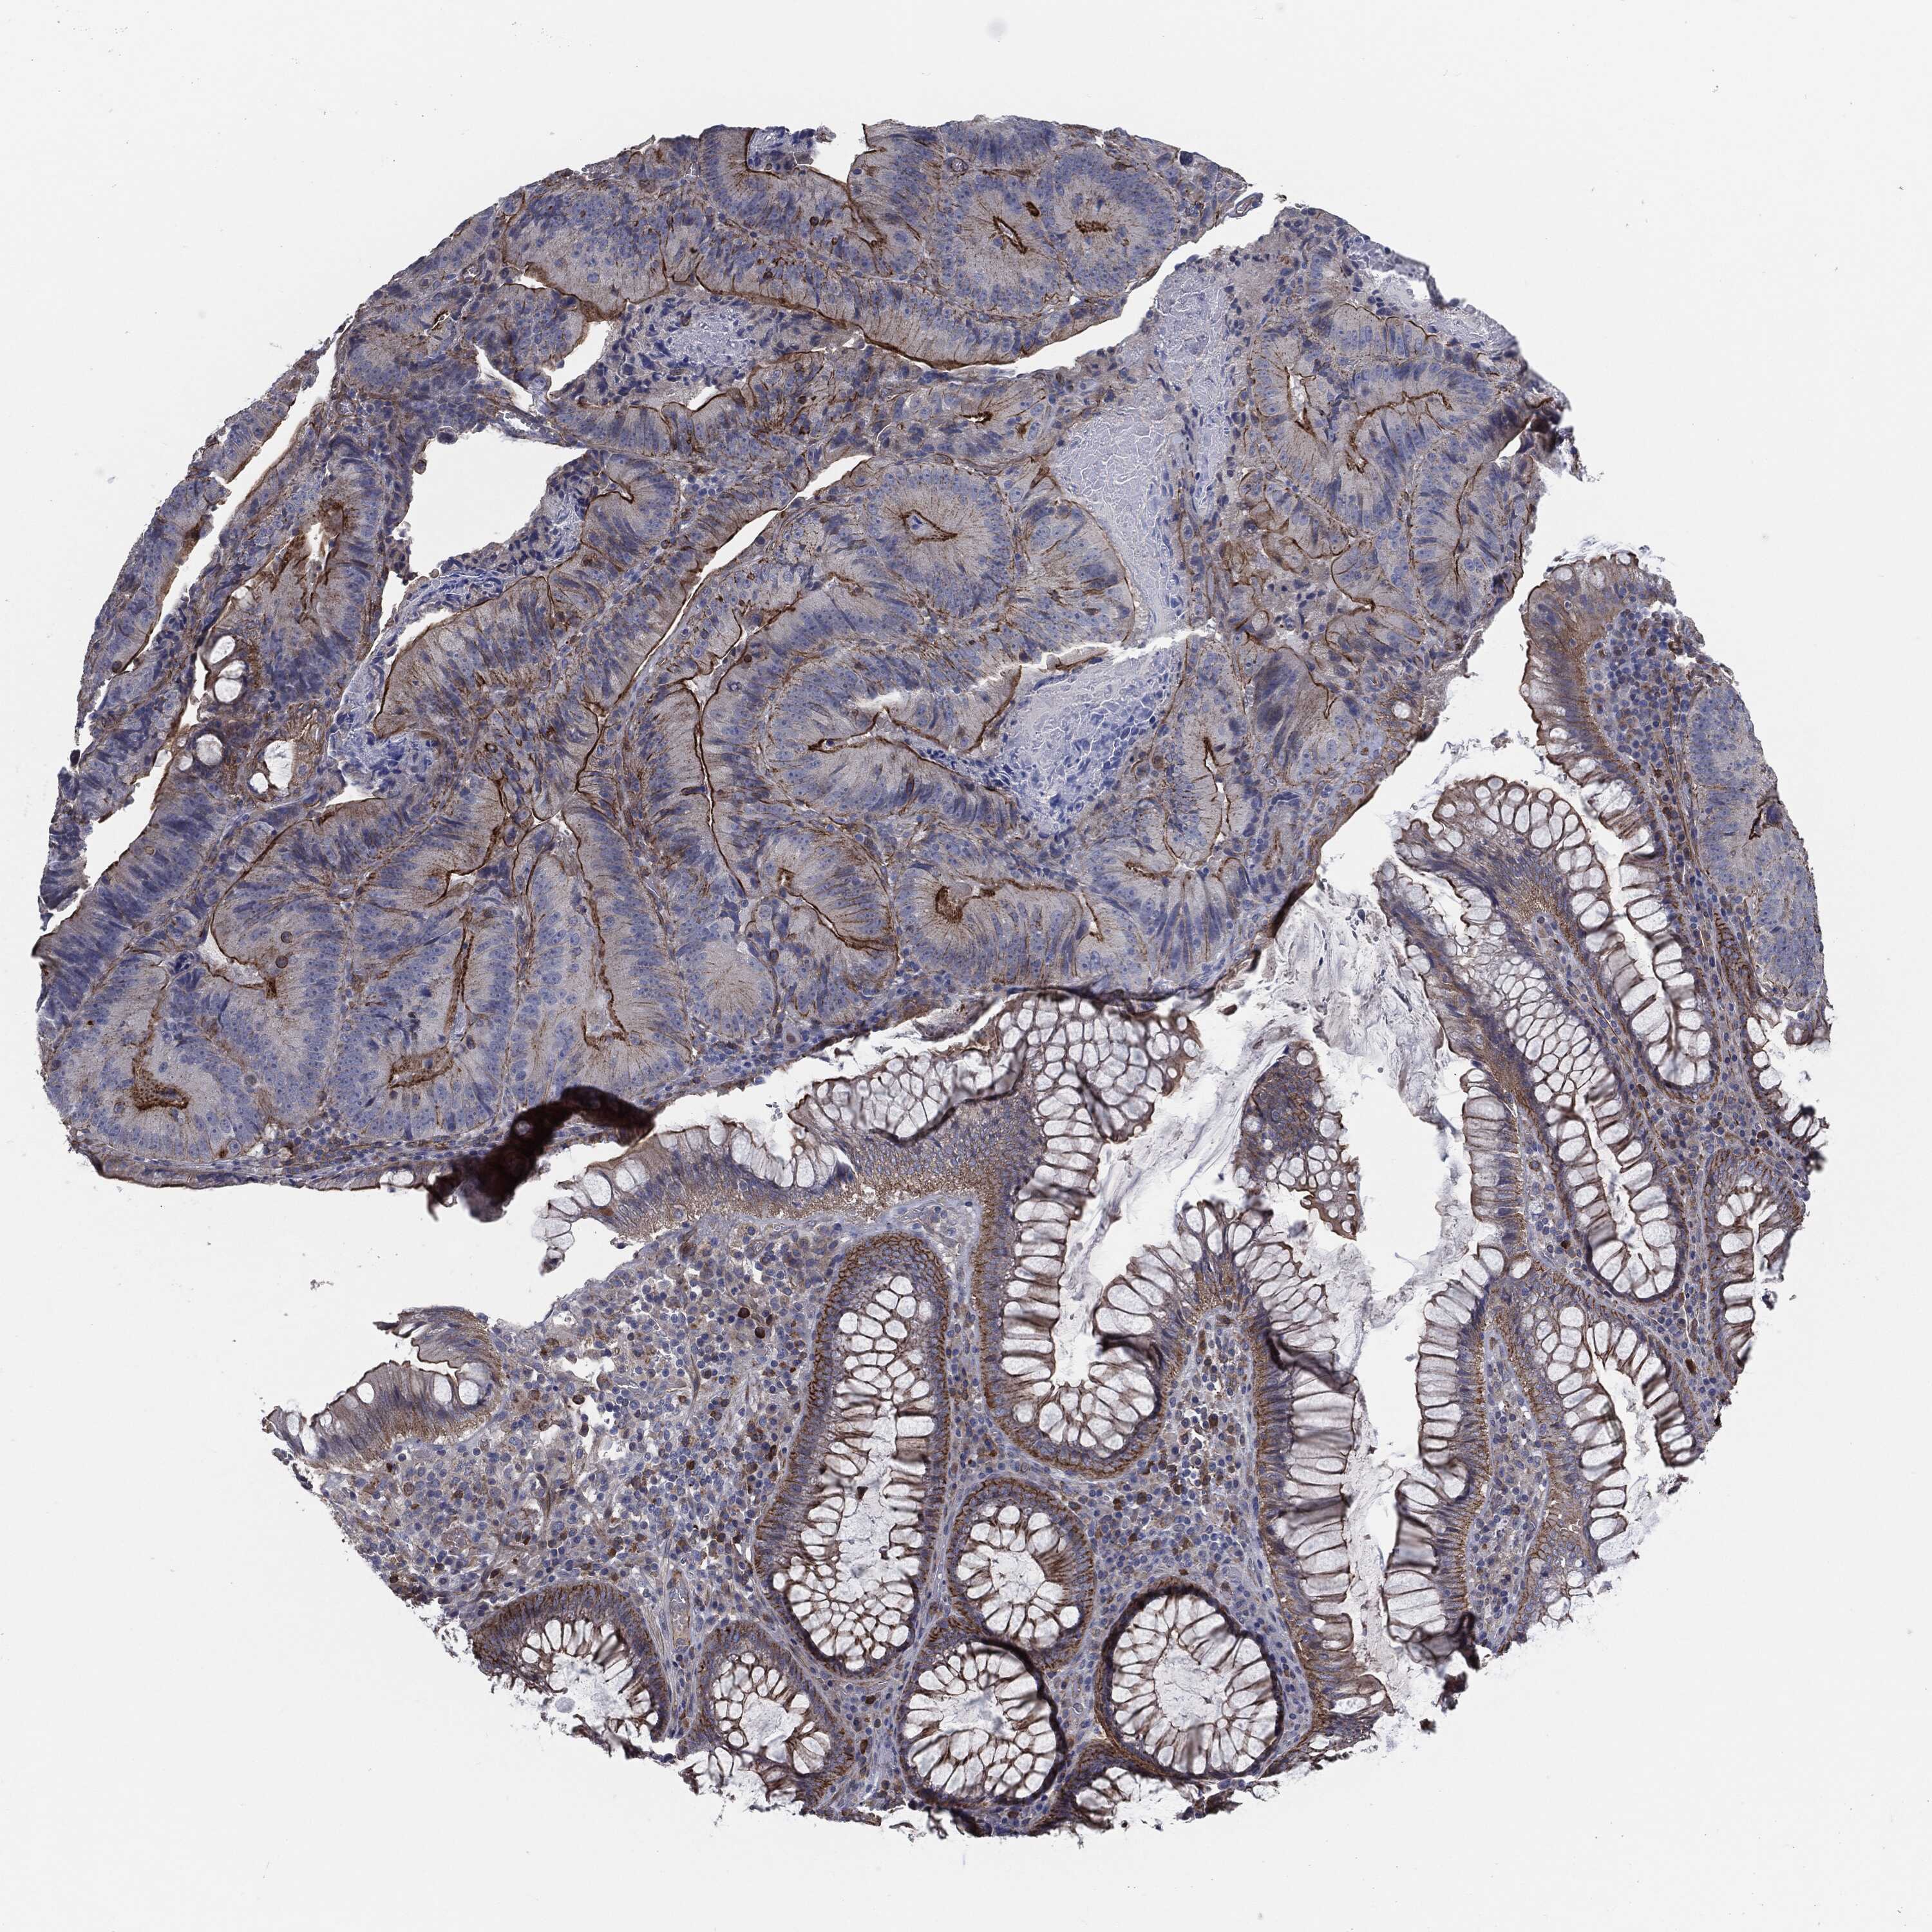

CANCER COLORECTAL CANCER Show tissue menu

Colorectal cancer

Human cancer

Colon adenocarcinoma

Rectum adenocarcinoma

COLON ADENOCARCINOMA (TCGA) - Interactive survival scatter ploti

The Survival Scatter plot shows the clinical status (i.e. dead or alive) for all individuals in the patient cohort, based on the same data that underlies the corresponding Kaplan-Meier plots. Patients that are alive at last time for follow-up are shown in blue and patients who have died during the study are shown in red.

The x-axis shows the expression levels (FPKM) of the investigated gene in the tumor tissue at the time of diagnosis. The y-axis shows the follow-up time after diagnosis (years). Both axes are complimented with kernel density curves demonstrating the data density over the axes. The top density plot shows the expression levels (FPKM) distribution among dead (red) and alive patients (blue). The right density plot shows the data density of the survived years of dead patients with high and low expression levels respectively, stratified using the cutoff indicated by the vertical dashed line through the Survival Scatter plot. This cutoff is automatically defined based on the FPKM cutoff that minimizes the p-score. The cutoff can be changed by dragging the vertical line or by entering a cutoff value in the square labeled "Current cut-off".

Under the Survival Scatter plot the p-score landscape (black curve; left axis) is shown together with dead median separation (red curve; right axis). Dead median separation is the difference in median mRNA expression between patients who have died with high and low expression, respectively. It is calculated as follows: median FPKM expression of dead patients with high expression - median FPKM expression of dead patients with low expression. This is intended to aid the user in visually exploring custom cutoffs and the associated p-scores and dead median separation.

Individual patient data is displayed and can be filtered by clicking on one or more of the category buttons on the top of the page. Categories describing expression level and patient information include: high, low, alive, dead, female, male and tumor stages. The scale of the x-axis can be toggled between linear and log-scale by clicking on the "x log" button. Mouse-over function shows TCGA ID, patient information and mRNA expression (FPKM) for each patient.

& Survival analysisi

Kaplan-Meier plots summarize results from analysis of correlation between mRNA expression level and patient survival. Patients were divided based on level of expression into one of the two groups "low" (under cut off) or "high" (over cut off). X-axis shows time for survival (years) and y-axis shows the probability of survival, where 1.0 corresponds to 100 percent.

SVIL is not prognostic in Colon Adenocarcinoma (TCGA)

Best expression cut offi

Based on the FPKM value of each gene, patients were classified into two groups and association between prognosis (survival) and gene expression (FPKM) was examined. The best expression cut-off refers the FPKM value that yields maximal difference with regard to survival between the two groups at the lowest log-rank P-value. Best expression cut-off was selected based on survival analysis .

When clicking on this number, the vertical dashed line indicating cut-off, the interactive survival plot, and the Kaplan-Meier curve will be adjusted to show results based on the best expression cut-off.

: 13.67

TCGA RNA samplesi

RNA-seq data is reported as average FPKM (number Fragments Per Kilobase of exon per Million reads), generated by the The Cancer Genome Atlas (TCGA) .

Normal distribution across the dataset is visualized with box plots, shown as median and 25th and 75th percentiles. Points are displayed as outliers if they are above or below 1.5 times the interquartile range. FPKM values of the individual samples are presented next to the box plot.

Average pTPM 20.4

Number of samples 254